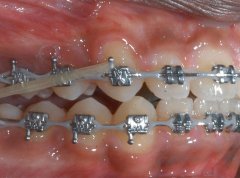

前牙开颌是解决牙齿畸形的最理想方法,通过医学的方法,用矫正器使牙齿进行...【详细】